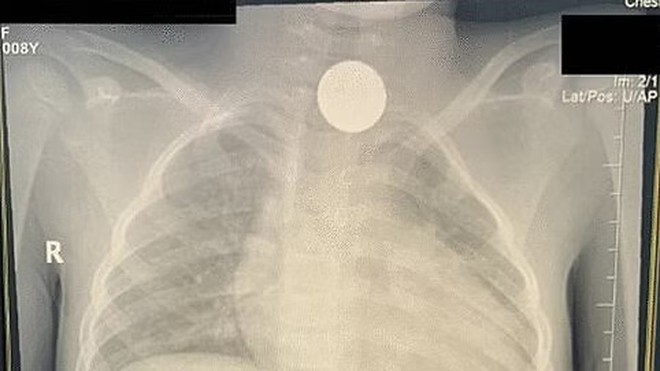

’لڑکی کے حلق میں کوئن کی موجودگی کا انکشاف اتفاقیہ ہوا ہے‘ ( فوٹو: سبق)

سعودی ڈاکٹروں نے کامیاب آپریشن کے ذریعہ 11 سالہ لڑکی کے حلق میں 4 سال سے پھنسا کوئن نکال لیا ہے۔

سبق ویب سائٹ کے مطابق لڑکی کے حلق میں کوئن کی موجودگی کا انکشاف اتفاقیہ ہوا ہے۔

طبی ٹیم نے کہا ہے کہ ’4 سال پہلے لڑکی نے غلطی سے کوئن نگل لیا اور گھر والوں سے بات چھپائے رکھی‘۔

’اتفاق سے  کوئن نگلنے سے اسے سانس لینے میں تکلیف ہوئی نہ ہی اس کے مابعد اثرات ظاہر ہوئے‘۔

’واقعے کے بعد بات آئی گئی ہوگئی اور خود لڑکی بھول گئی کہ اس نے کوئن نگل لیا تھا‘۔

ڈاکٹروں نے کہا ہے کہ ’گزشتہ دو سال سے لڑکی کوانیمیا کی شکایت ہوئی اور متعدد مرتبہ ڈاکٹروں کو دکھایا‘۔

’ایک مرتبہ ایکسرے کے دوران حلق میں پھنسا کوئن بھی ایکسرے میں واضح طور پر نظر آیا مگر ڈاکٹروں نے سمجھا کہ لڑکی نے شاید کوئی لاکٹ وغیرہ پہنا ہوا ہے‘۔

’بعد ازاں لڑکی کا ایکسرے ہوا تو انکشاف ہوا کہ اس کے حلق میں کوئی بھنسا ہوا ہے‘۔

طبی ٹیم نے کہا ہے کہ ’کوئی نکالنے کے لیے گلے میں آپریشن کیا گیا جو کامیاب رہا اور چار دن بعد لڑکی کو گھر جانے دیا گیا‘۔